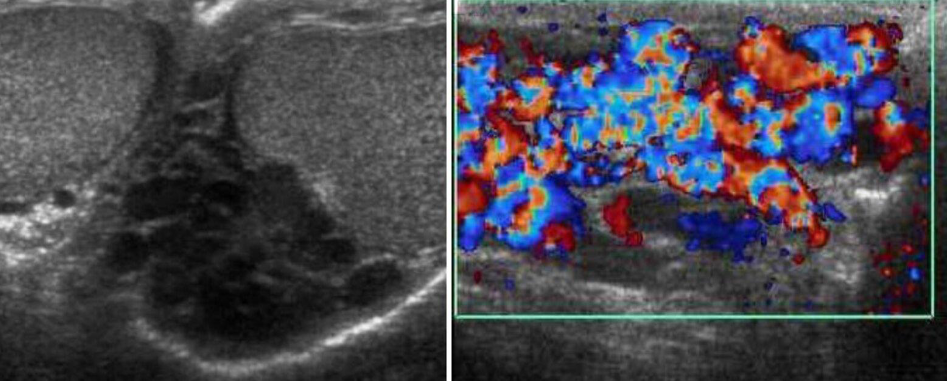

Patient presented with scrotal pain

and swelling - Ranges from mild tenderness to a severe febrile process with acute unilateral scrotal pain. -

A. Give the name of imaging examination. Color Doppler ultrasound

B. Describe the abnormality imaging shows Reactive hydrocele and scrotal wall thickening , edematous epididymis and shows increase vascularity on Doppler

C. What is the most probable diagnosis in the ? Epididymitis